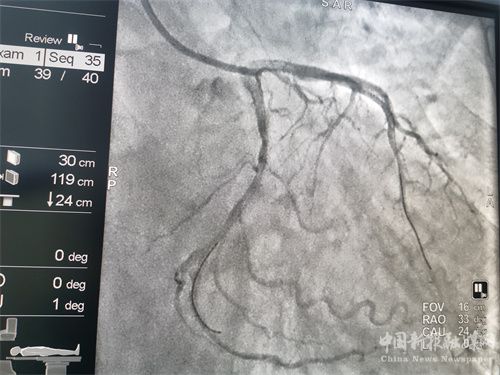

術(shù)后

患者溶栓成功后,經(jīng)患者及家屬同意后行冠狀動脈造影檢查,患者冠脈顯示前降支次全閉、回旋支狹窄95%、右冠近端狹窄85%,病情緊急,李維軍、楊亮主任向家屬詳細(xì)講明病情后,予以開通前降支和回旋支,植入支架3枚。手術(shù)全程用時不到一個小時。目前,患者病情穩(wěn)定。